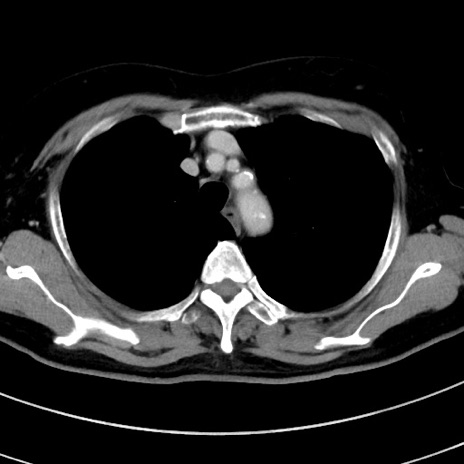

症例9(横断像)

【症例】 60歳代女性

【主訴】むかつき、みぞおちの痛み

【現病歴】3日前よりむかつきがあり、食事がとれない。

【既往歴】糖尿病

【身体所見】発熱なし、心窩部圧痛軽度あるも、腹膜刺激症状なし。

【データ】WBC 7400、CRP 1.92